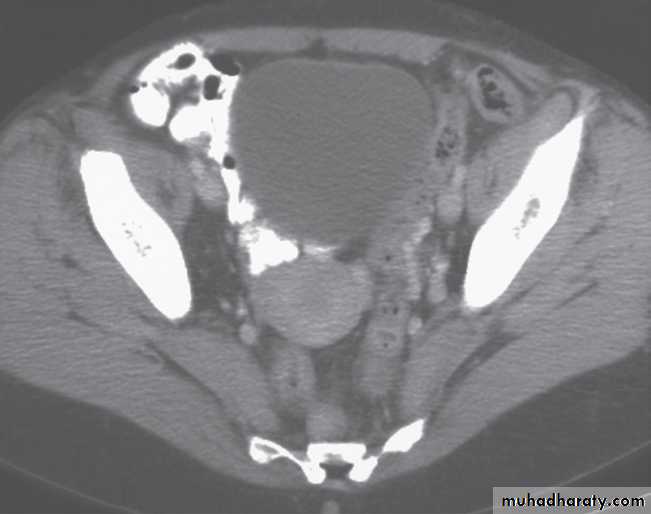

Multislice CT of the pelvis may be optimized with the use of oral contrast (water or dilute iodine-based contrast) given 1 hour prior to pelvic imaging to aid the differentiation of bowel loops from adnexal structures. Intravenous contrast medium may help to differentiate between vessels and lymph nodes, and to assess the enhancement pattern of a mass. Viewing on coronal and sagittal reformatted images is also helpful.-The vagina is seen as a linear structure between the urethra and rectum.

- The cervix is seen Immediately above the vagina, as a rounded soft tissue structure approximately 3 cm in diameter.

The body of the uterus .merges with the cervix and its precise appearance depends on the lie of the uterus. The endometrial lining cannot be fully assessed on CT.

-The fallopian tubes and broad ligaments are usually not visible .

-The ovaries may not be identified. The parametrium is of fat density, the interface with the pelvic musculature being clearly visible.The uterus may be surrounded by loops of bowel.